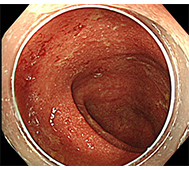

- 内視鏡治療 :病変がリンパ節転移の無い早期食道がんに対し、内視鏡治療が行われます。

初期症状は食道違和感や喉のつかえ感などの不定愁訴に近いため、発見が遅れやすく、食道がん自体がリンパ節転移が多いことや、周囲に浸潤しやすいことから、早く進行します。

早期がんの場合はそれに伴う身体所見はほとんどありません。

進行がんの場合は、嚥下困難などを認めます。